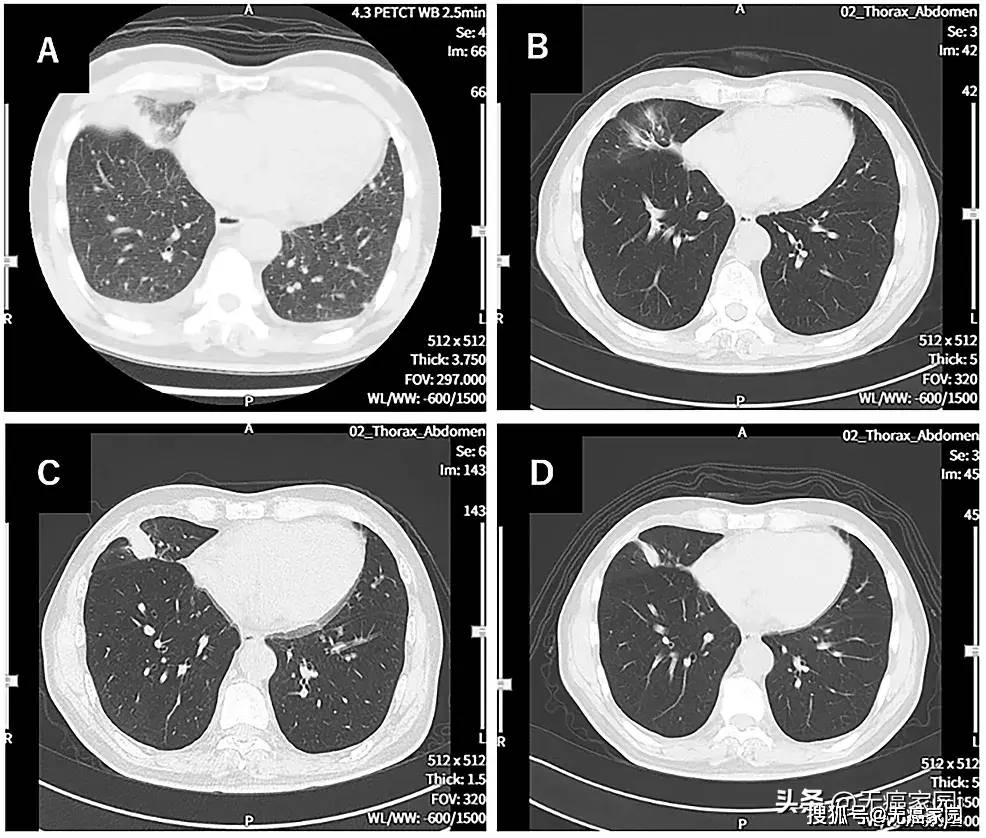

clin chest med:肺部的这些表现可能提示肺外恶性实体瘤